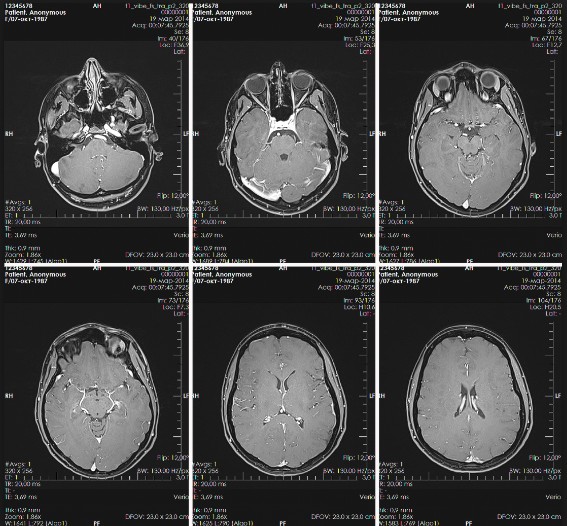

МРТ головного мозга: что показывает исследование

Нормальная МРТ головы - что показывает исследование

Пациентов часто интересует вопрос, как выглядит нормальная томография головного мозга. В норме результаты исследования содержат следующие данные:

Что покажет МРТ головыЧто еще видно на МРТ головного мозга здорового человека, помимо указанных пунктов? Врач отмечает однородность тканей, отсутствие инородных тел, различных включений, очагов кровотечения, участков затемнения либо просветления, каких-либо патологических образований.

Посмотреть примеры заключений по МРТ головного мозга и примеры изображений можно на различных медицинских ресурсах Интернета.